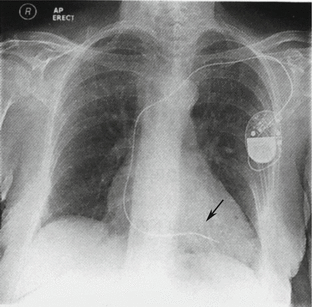

Fig. 4.20

X-ray shows right ventricle pacemaker that has been implanted under the left shoulder. The electrode passes through the subclavian vein while its head end in the apex